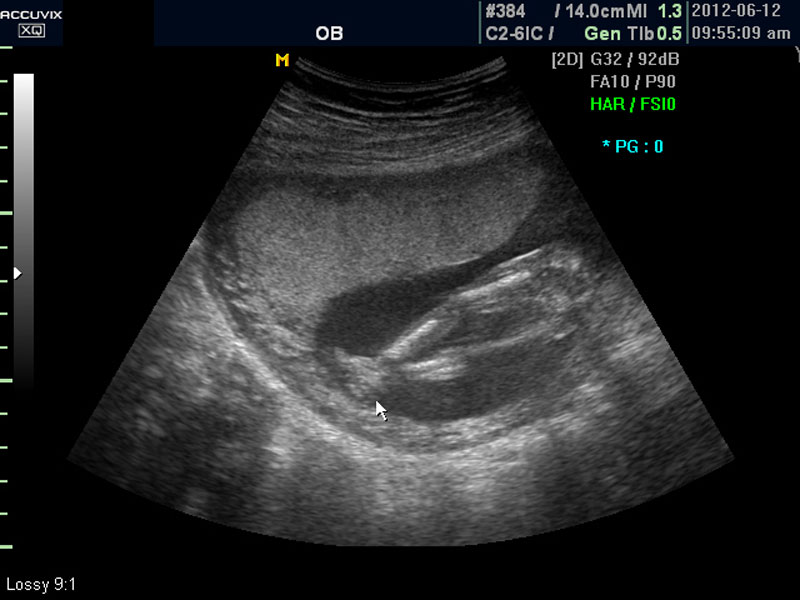

태아에 대한 관찰이 끝나면 태반의 위치와 양수의 양을 살펴 보는데 아직 태반의 위치는 고정된 것이 아니라 크게 의미는 없지만 이때부터의 위치는 대체로 임신 후반까지 크게 바뀌는 것은 아니며 또한 완전 전치 태반과 같은 경우는 임신 중기부터 출혈등의 증상이 나타날 수 있어 관찰이 필요한 대상입니다.

화면에서는 위쪽에 하얗게 균일하게 보이는 것이 태반의 모습입니다.

태반은 실제로 보면 피자처럼 둥그런 원판 모양이며 임신 후기로 갈수록 태아와 마찬가지로 크기가 커지고 두꺼워집니다.

양수의 양은 태아의 건강과 관련된 지표로 너무 많거나 너무 적으면 좋지 않은데 그 절대양을 측정할 수는 없어서 양수가 많은 부분의 깊이를 측정하거나 혹은 개략적으로 전체에서 차지하는 부분을 봐서 이상 여부를 판단합니다.

사진에서 검게 보이는 것이 양수입니다. 양수에 대하여는 색깔이나 밀도 등 다른 요소는 알기 어려워서 그 양만 가지고 판단을 하게 됩니다.

임신 초기나 중기의 양수 이상 중에는  대체로 태아의 건강 이상으로 인한 양소 과소증이 더 많은 편입니다.